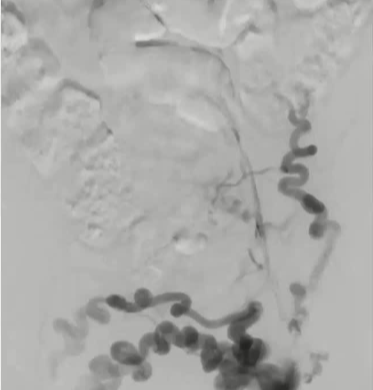

其它考虑怎么做?How to do IT? 1. 建议将静脉段的扩张程度控制在与所选支架直径相匹配的范围内。【Rahmani 2023 Gibson 2022 Cirse SOP 2014 Raju 2013】 狭窄血管的过度扩张通常不会导致破裂,即便在慢性闭塞的情况下,血管也能承受较大的球囊扩张,并在随后置入较大的支架而不会发生破裂。 只有在以下情况才需例外处理:即在腹膜后区域或鞘管 环绕外科手术已经打开的静脉【joyce DP 2024】 对于慢性静脉阻塞的情况,采用逐渐增大直径的球囊进行多次扩张操作可能并非必要。 除非您无法将 14/16 毫米的气囊顺利穿过病变部位,否则可能需要进行多次扩张操作。【Barbati 2014】 2. 此外,该操作应贯穿整个病变部位的整个长度进行。【Oropailo 2023 Lichtenberg 2018】 ![]() 3. 使用高压球囊【Oropallo A 2023 Gibson 2022】 44岁 男 2次左髂股静脉血栓形成,以下静脉造影